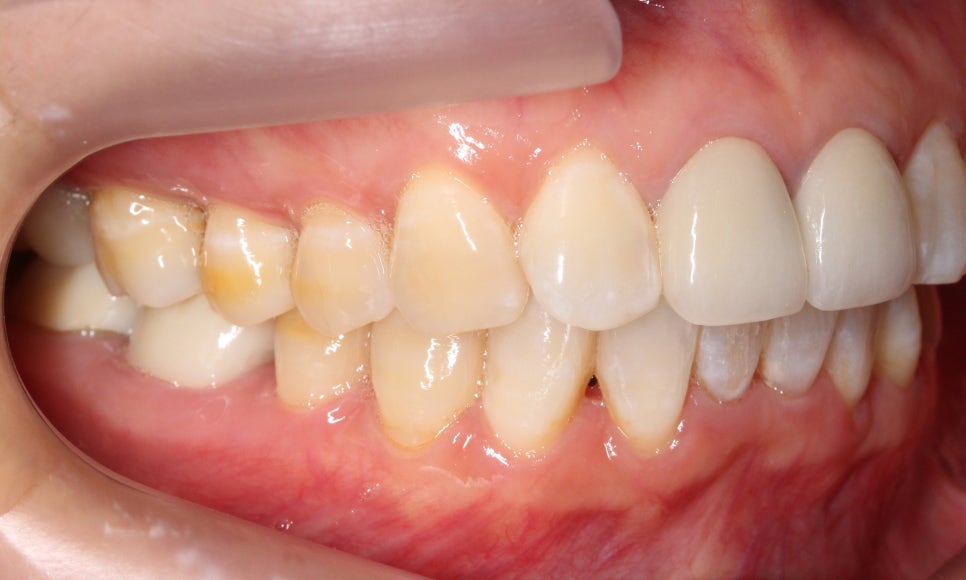

측면의 모습을 보면 아랫니의 앞쪽이

윗니의 뒷쪽으로 많이 들어가 있는 것을

확인할 수 있습니다!

반대쪽도 같은 모습인데요,

이렇게 아랫니가 윗니를 향해

깊숙히 물린다면 아랫니의 절단연에 의해

윗니의 잇몸이 상처를 입을 수 있습니다.

반대쪽 모습도 과하게 물리는 모습 없이

깔끔하게 교정되었어요 : )